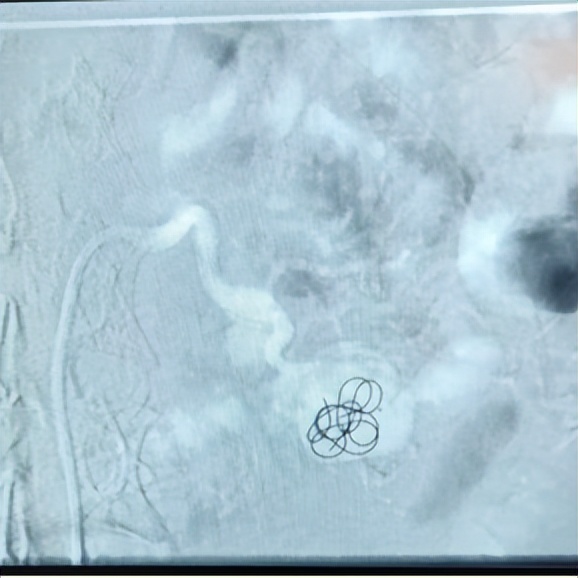

将微导管小心插入动脉瘤腔内,逐渐释放弹簧圈填塞瘤腔。

栓塞后再次造影:动脉瘤完全被填塞,瘤内血流消失,正常肾脏血流不受影响。王先生术后卧床休息了一天,也无需禁食,第二天就可以下床自由活动,而被栓塞后的动脉瘤再无血流,也就没有出血的风险, 藏在体内的“定时*弹炸**”得以最小的代价被拆除。